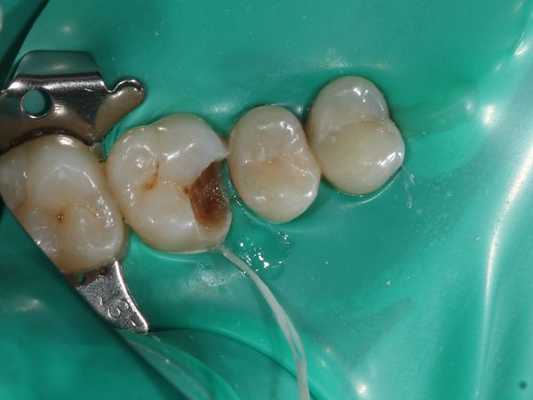

При осмотре зуба 1.6 обнаружена обширная кариозная полость на апроксимально-мезиальной поверхности (поверхность, которая прилегает к соседнему зубу и обращена к центру зубного ряда). Кариозная полость заполнена размягчённым дентином.

- Изоляция зуба 1.6 коффердамом. Коффердам представляет собой салфетку из латекса, которая позволяет изолировать нужный зуб для лечебных манипуляций.

- Препарирование кариозной полости и некрэктомия, что подразумевает раскрытие полости и удаление патологически изменённых эмали и дентина.

- Контроль препарированных тканей кариес-маркером (жидкостью, которая окрашивает участки зуба, поражённые кариесом).

- Вскрытие полости зуба, формирование доступа к корневым каналам зуба 1.6.

- Механическая экстирпация (удаление) коронковой части пульпы зуба 1.6.